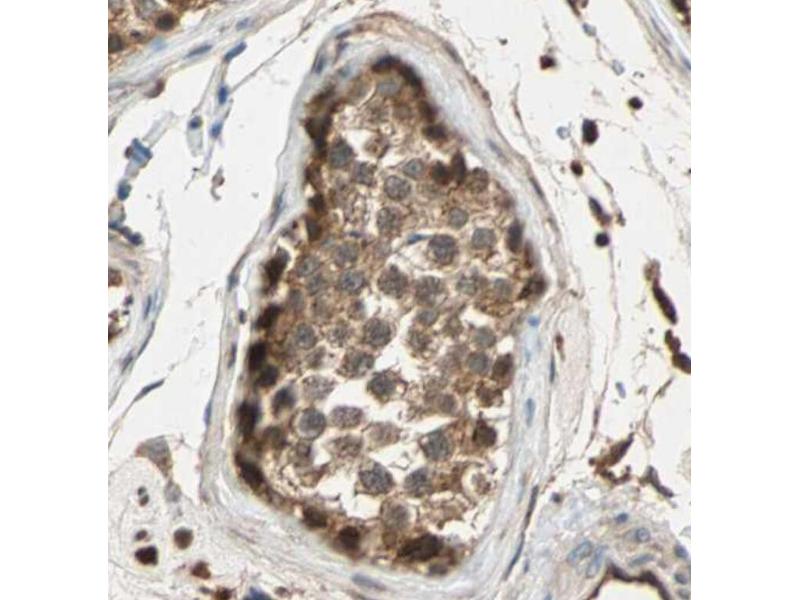

MAPK3 Reaktivität: Human, Maus, Ratte IHC Wirt: Kaninchen Polyclonal unconjugated